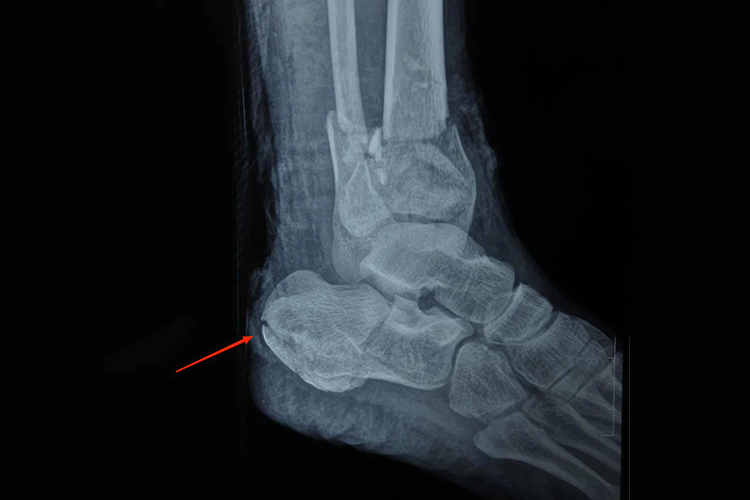

左跟骨骨折通常是由于外力作用或自身骨骼疾病等原因导致,包括高处坠落、交通事故、运动损伤、骨质疏松等方面,患者应积极配合治疗,做好康复护理,以促进恢复。

1、高处坠落:从高处坠落时,足跟先着地,巨大的冲击力集中在跟骨,容易造成骨折。骨折后应立即制动,避免负重,尽快就医。若骨折较轻,可采取保守治疗,如石膏固定。

2、交通事故:车祸中受到撞击或挤压,可导致左跟骨骨折。此时需进行详细的检查,判断骨折类型和严重程度。对于轻度骨折,可通过支具固定;严重骨折可能需要手术复位内固定。

3、运动损伤:在进行剧烈运动,如篮球、足球等,突然的扭转或碰撞可能引起跟骨骨折。伤后应冷敷、抬高患肢,减轻肿胀。治疗方法根据骨折情况而定,包括保守治疗和手术治疗。

4、骨质疏松:老年人或长期患有影响骨代谢疾病的人群,骨密度降低,骨骼脆弱,轻微的外力就可能导致跟骨骨折。治疗时除了处理骨折,还需治疗骨质疏松,以促进骨折愈合和预防再次骨折。